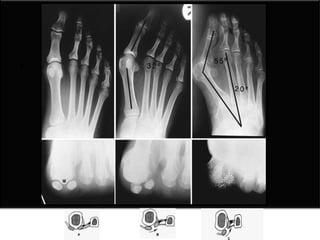

Angulo del hallux valgus (15 -20°)

Angulo intermetatarsal (8-9°)

Angulo articular metatarsal distal (DMMA) (10-15°)

Congruencia articular

Cambios degenerativos

Primera unión MTT-falange

Longitud del 1° - 2° metatarso

Posición del sesamoideo

Osteotomía en Vinvertida Hallux valgus angle Intermetatarsal angle Distal metatarsal articular angle

Angulo del halluxvalgus (15 -20°) Angulo intermetatarsal (8-9°) Angulo articular metatarsal distal (DMMA) (10-15°) Congruencia articular Cambios degenerativos Primera unión MTT-falange Longitud del 1° - 2° metatarso Posición del sesamoideo